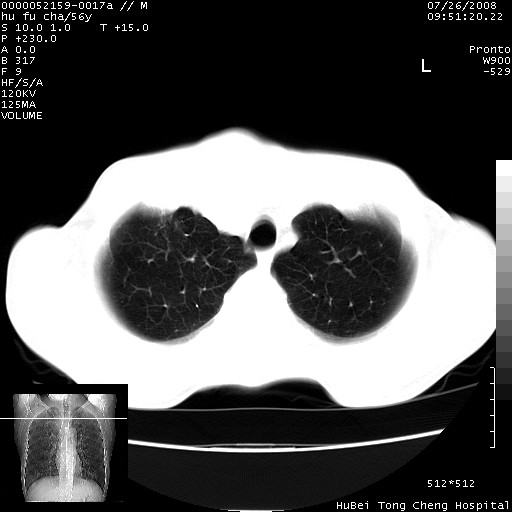

以下是引用zsl6918在2008-8-25 22:47:00的发言:[br]胸骨,胸椎及肋骨均可见多发转移表现,肝内低密度结节不除外转移。原发灶可能在右肺。双侧可见支扩表现。